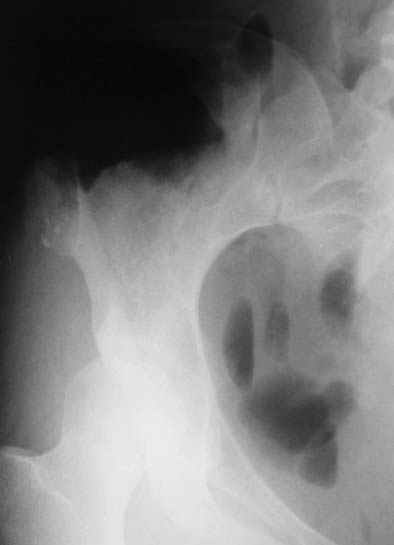

Получены результаты гистологического исследования.Процесс доброкачественный. Диагноз хондрома крыла таза подтвержден.Вопрос: чем и как закрыть предполагаемый значительный дефект крыла?

P.S. ещё фото

Уважаемые коллеги, больную прооперировали. После выделения остеохондрома резецирована в пределах неизменённой кости. Выявлено, что гребень подвздошой кости не пострадал от опухоли. В результате резекции сформирован сквозной дефект в крыле подвздошной кости треугольной формы 6х7х8 см. В качестве трансплантата использована наружная кортикальная пластинка заднего отдела крыла подвздошной кости.

Трансплантат фиксирован на месте дефекта при помощи шурупов и проволоки. Кровопотеря 550 мл.